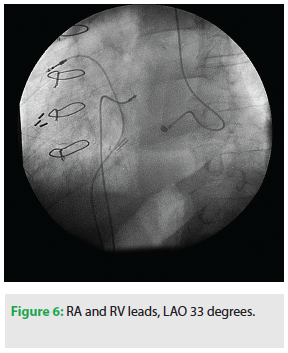

To implant the pacemaker, we accessed the right iliac vein twice, just above the inguinal crease. We advanced a Tendril STS pacing lead (2088TC/100, St. Jude Medical) through a 7 Fr Prelude SNAP™ introducer (Merit Medical) into the right atrium and assessed fixation of the lead by the current injury recorded from the right atrial electrogram. After obtaining satisfactory sensing and pacing thresholds, the sheath was split and removed.

A second Tendril STS pacing lead (2088TC/100, St. Jude Medical) was advanced to the right ventricle through a second 7 Fr Prelude SNAP™ introducer (Merit Medical) and positioned in the right ventricular septum. After obtaining satisfactory sensing and pacing thresholds, the sheath was split and removed. Care was taken to provide enough slack of the leads to prevent dislodgement.